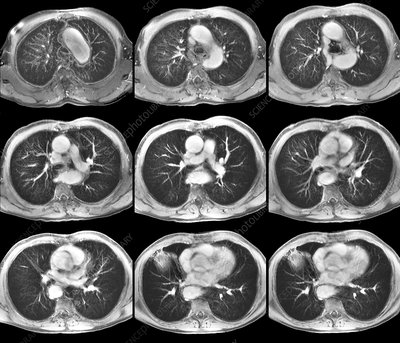

2D Cancer Annotation

3D Visualization for Surgical Planning

CT Scanner

Image Volumes

2D

3D

Download the same data to 3D Slicer using the IDC Browser extension!

Then, we will do Volume Rendering to analyze data and create a segmentation mesh of the tumor.

After export, let's load it in SliceDrop!